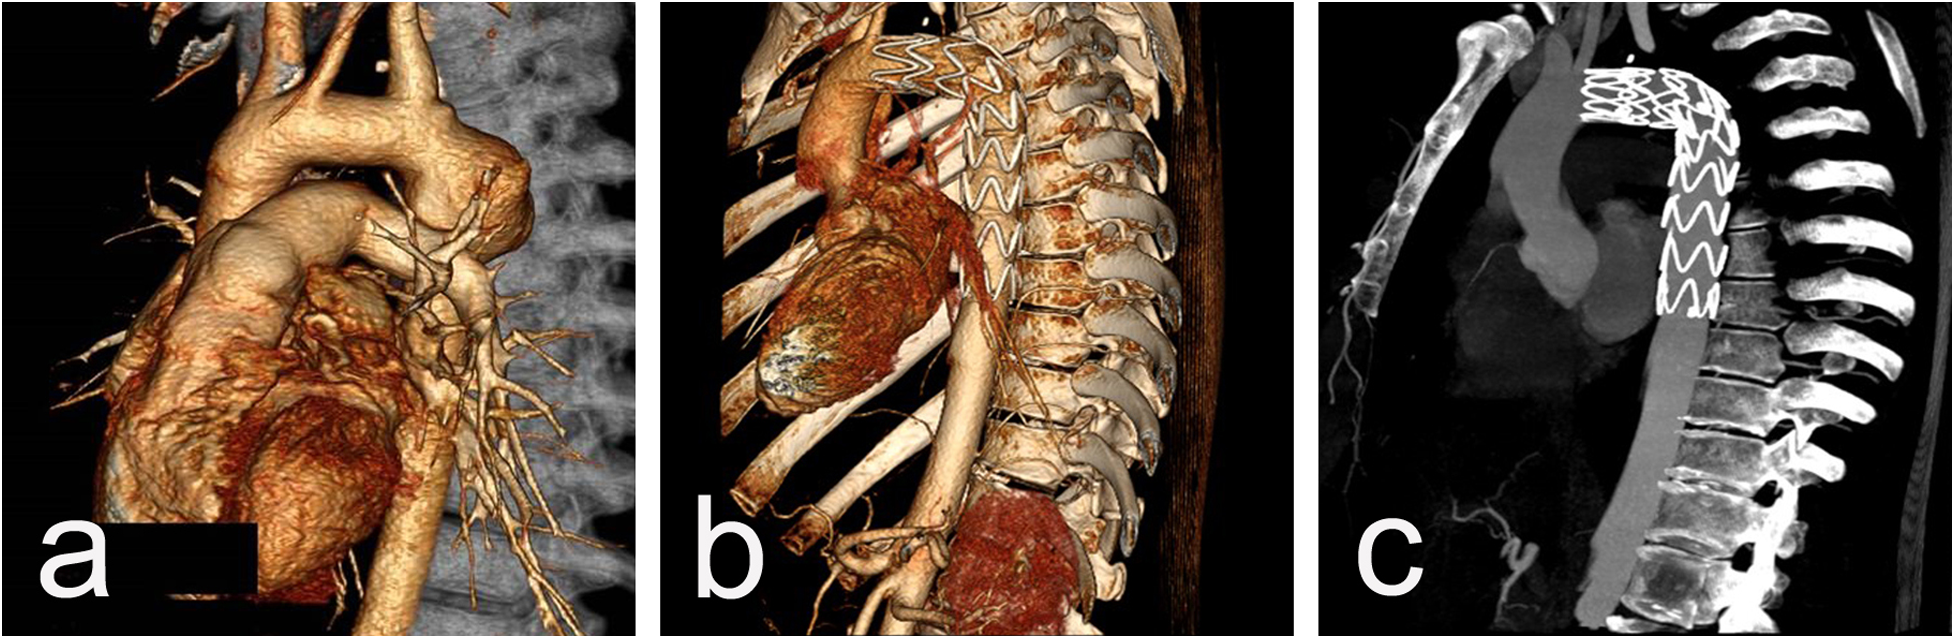

Procedural data: All cases were performed in a standard catheter lab environment. Stent-graft deployment was successful in all patients. In 5 patients, partial or complete coverage of the LSA was necessary to ensure an adequate landing zone for the endoprosthesis and to avoid endoleak. Two of them underwent aorto-carotid bypass to the left common carotid artery, performed prior to aortic stenting. No subclavian steal syndrome was observed during the hospital stay and subsequent follow-up (Figures 1a–c). Four patients required additional stent(s). Postdeployment aortography revealed type I endoleak in 4 patients, with one left under surveillance. while in the other three, additional endoprostheses were implanted to seal the leak (one received 2 additional endoprostheses, and the others received 1 endoprosthesis) with optimal results. In one of those patients, we observed a severe type I endoleak with a persistent filling of the aneurysm due to a collapse of the stent-graft (26/155 mm) in the large aneurysm, accepting its large curvature. A second endoprosthesis (28/200 mm) was positioned using two stiff guidewires to cross the old prosthesis. The additional stent-graft was positioned right behind the left carotid artery, and we achieved complete aneurysm isolation (Figures 2a–e). There was no procedural mortality and neurologic, vascular-access, or ischemic complications. All patients were cared for in the intensive care unit after the procedure, with a mean stay of 1.84 days. The average hospital stay was 9.3 days (7–19 days) (Table 3).

Figure 1

CT scan imaging before (a) and after (b and c) stent-graft implantation of 26y/o male presenting acutely with contained rupture of an aneurysm 20 years after initial CoA repair. The aortic aneurysm is located close to the origin of LSA (a) and the implanted graft excluded the aneurysmal sac but fully covered the LSA (b) with an excellent blood supply through the left vertebral artery from control CTAs (c).